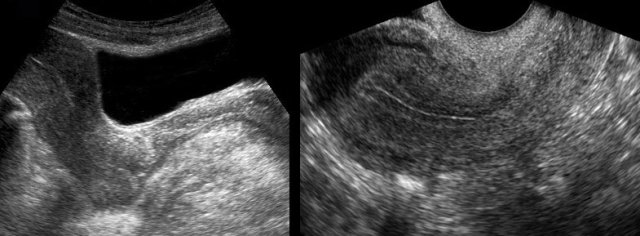

Pyosalpinx

case 1

these images are of a young woman with pain in the RLQ for two days and CRP 170 and WBC 14.

US respectively

TVUS shows tortuous, thick-walled tubular

structure right of the uterus (ut.), in combination with the CRP, typical for a

pus-filled Fallopian tube (pyosalpinx).

This

patient was successfully treated with antibiotics but had recurrent episodes.

For this reason she underwent

a tubectomy three years later.

case 2

Young lady with pain RLQ since three days. CRP 100 and WBC 23, suspect for appendicitis.

US shows

turbid peritoneal fluid and a dilated, thick-walled Fallopian tube, filled with debris. Complete cure after antibiotics.

case 3

Young woman with acute pain RLQ and a CRP 180, suspect for appendicitis.

US

confirms a IUD in the uterus and a large, right-sided pyosalpinx.

Complete

recovery after antibiotics and removal of the IUD.